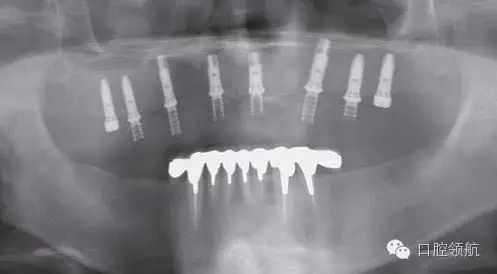

首先確認是否有炎癥表現(xiàn),結(jié)果是沒有問題(圖1)。

圖1 戴入種植體支持的上頜全口整體連接的臨時上部結(jié)構(gòu)。1周后來院時訴前頭部有勒緊樣疼痛。

X線影像也未見異常(圖2)。

圖2 X線影像未見異常。